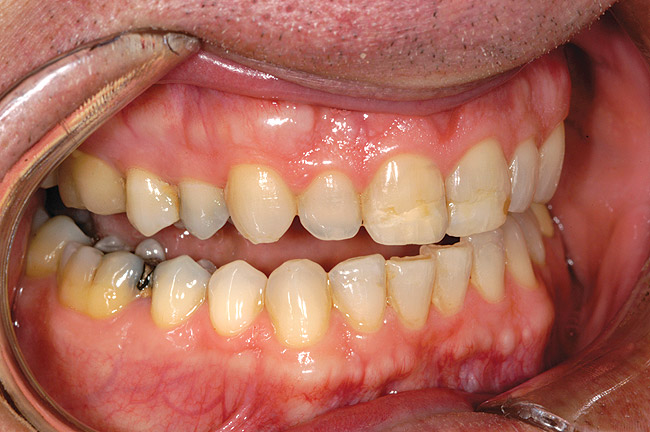

Figure 7a  Teeth Nos. 4, 5, and 30 were in need of indirect restorations and were treatment planned for all-porcelain, adhesively retained restorations.

Figure 7a

Figure 7b  A desire to increase the buccal contour of tooth No. 5 and the visibility of the maxillary bicuspids within the esthetic zone suggested that facial margins be placed at the free gingival margin.

Figure 7b

Figure 7c  Harmonious blending of indirect restorations and natural tooth structure provides improved esthetics and conservation of tooth structure.

Figure 7c

Figure 7d  Note that the facial margin was carried to the free gingival margin on the maxillary bicuspids. However, in areas of less esthetic significance, such as the tooth No. 30, the margin was kept supragingival in an effort to further conserve tooth structure.

Figure 7d